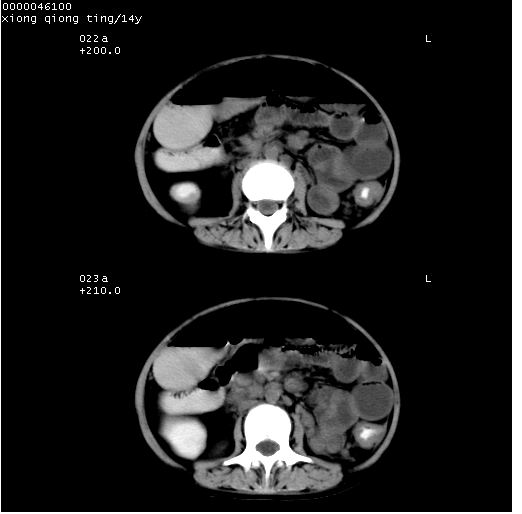

患儿 女,14岁。不规则发热一周,偶感头痛,无抽搐及呕吐。pe:神清,精神差,双侧瞳孔等大等圆,对光反射敏感,双肺未闻及明显啰音,心音有力,腹部触之似揉面感,下腹压痛,无反跳痛。

中下腹及盆腔ct轴位平扫+增强扫描(层厚10mm,螺距1.0,重建间隔10mm),图像如下:

(注:患儿检查当日上午9时口服胃肠道对比剂,下午3时许行ct扫描检查,未行对比剂直肠保留灌肠,检查当日患儿腹泻)

中下腹及盆腔ct轴位扫描(ps+ce)提示:腹部肠管明显充气扩张,并见数个不同宽度之气液平面;疑不全性肠梗阻或肠郁张。临床会诊考虑为患儿腹泻,肠郁张所致;后来未经特殊处理,患儿大便恢复正常,亦无腹胀。